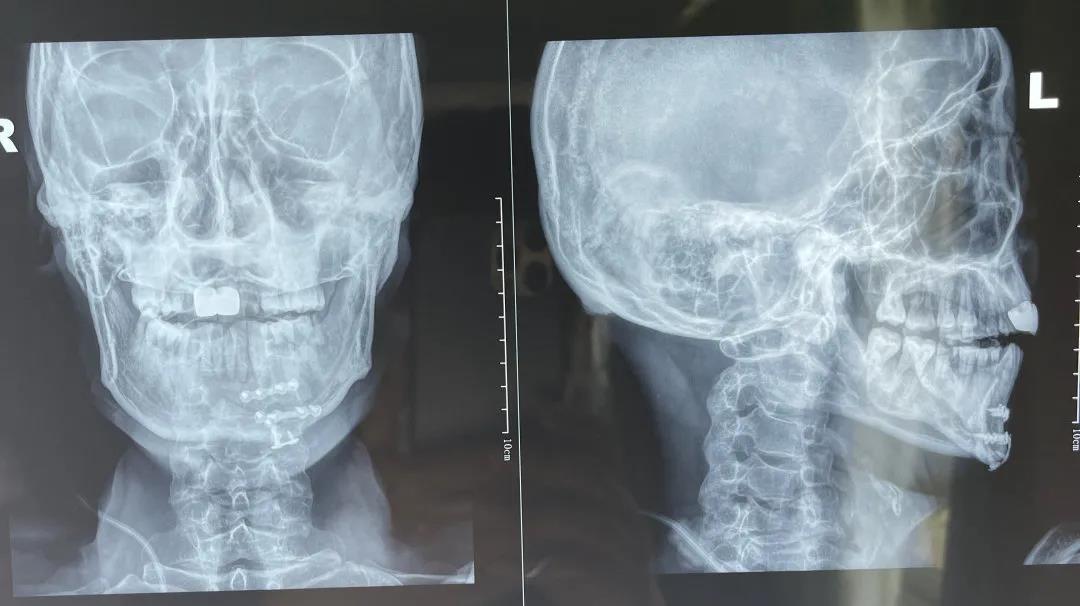

▲术前影像学资料

7月18日,石某在户外高空作业,不慎坠落,由120急救车送入万丰医院急诊抢救室。当时,患者神志不清,意识淡薄,头面部、胸腹部、髋部、左侧上下肢、口腔、鼻腔等多处出血,咬合关系紊乱,不能言语。影像学检查显示,病人不仅骨盆、下颌骨、左趾骨、左跟骨、腰椎、鼻骨等多处骨折,还伴有左上肺感染性病灶,双上肺肺大泡,病情危重,石某老婆得知病情这么重,心急如焚,几度哽咽。